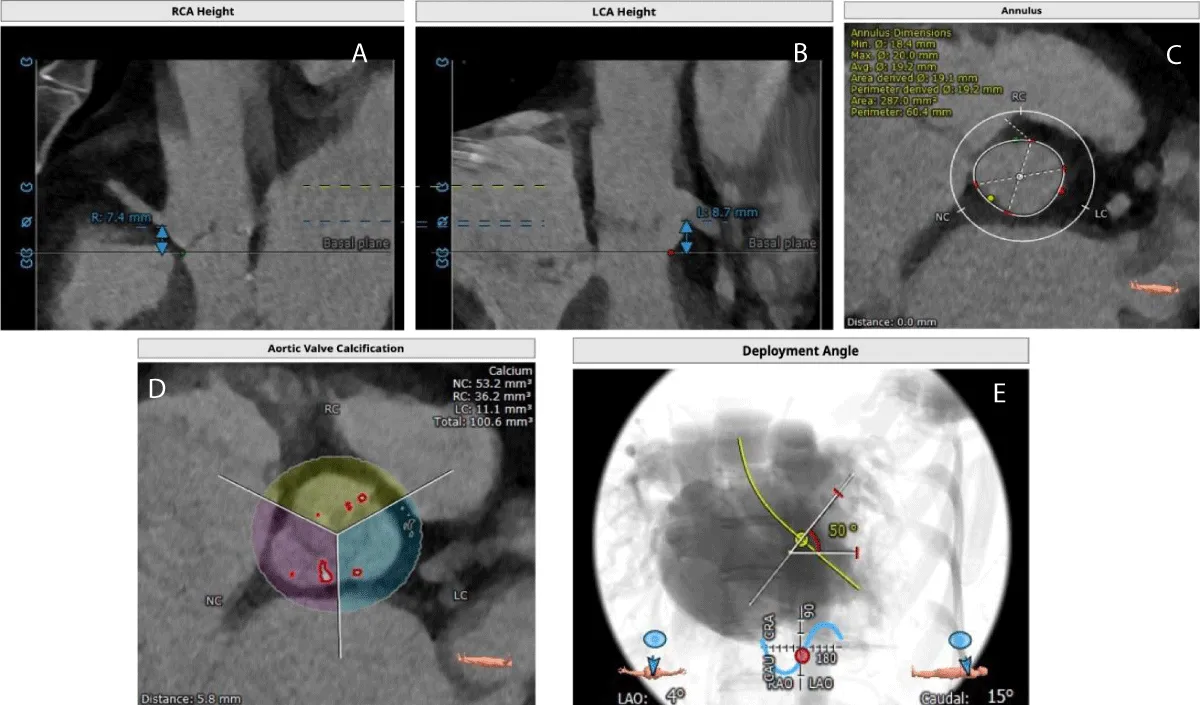

The MSCT scan showed Coronary Arteries (CA) with low heights (right CA: 7.4 and left CA: 8.7 mm) (Figure 1). The patient was considered suitable for transfemoral TAVR as per the Heart Team’s decision and a 20 mm BE Myval THV was selected in consideration of the low coronary heights. Written informed consent was obtained from the patient and the family.

Figure 1: Computed Tomography images shows- A) Right coronary artery height, B) Left coronary artery height, C) Aortic annulus area, D) Aortic valve calcification and E) Deployment angles.